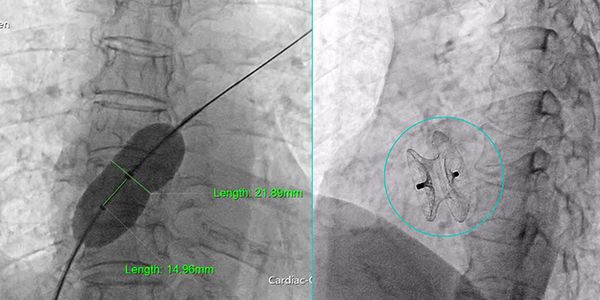

Kích thước lỗ thông 22cm qua kết quả thông tim dưới màn tăng sáng và hình sau can thiệp bít lỗ thông bằng dụng cụ dù.

Trước tình trạng khẩn cấp của bệnh nhân, các bác sĩ đã lập tức tiến hành hội chẩn đa chuyên khoa để thống nhất phương án điều trị tối ưu. Qua đó, ê-kíp quyết định thực hiện thủ thuật đóng lỗ thông liên nhĩ bằng dụng cụ qua da. Bệnh nhân được siêu âm tim kỹ lưỡng nhằm xác định chính xác kích thước, cấu trúc xung quanh bờ lỗ thông, từ đó lựa chọn dụng cụ đóng lỗ thông phù hợp nhất.

Sau can thiệp, bệnh nhân tỉnh táo, có thể giao tiếp với bác sĩ vì hoàn toàn không phải gây mê, nhịp tim và huyết áp ổn định, không đau ngực, không khó thở. Kết quả siêu âm kiểm tra lại cho thấy dụng cụ đóng lỗ thông đúng vị trí, bám tốt các rìa, không ảnh hưởng van tim, không còn thấy dòng máu thông thương giữa 2 buồng nhĩ trái và nhĩ phải như trước. Sức khỏe bệnh nhân diễn tiến tốt và được xuất viện hai ngày sau đó.